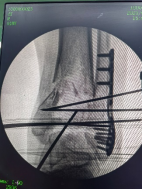

透視檢查骨折端